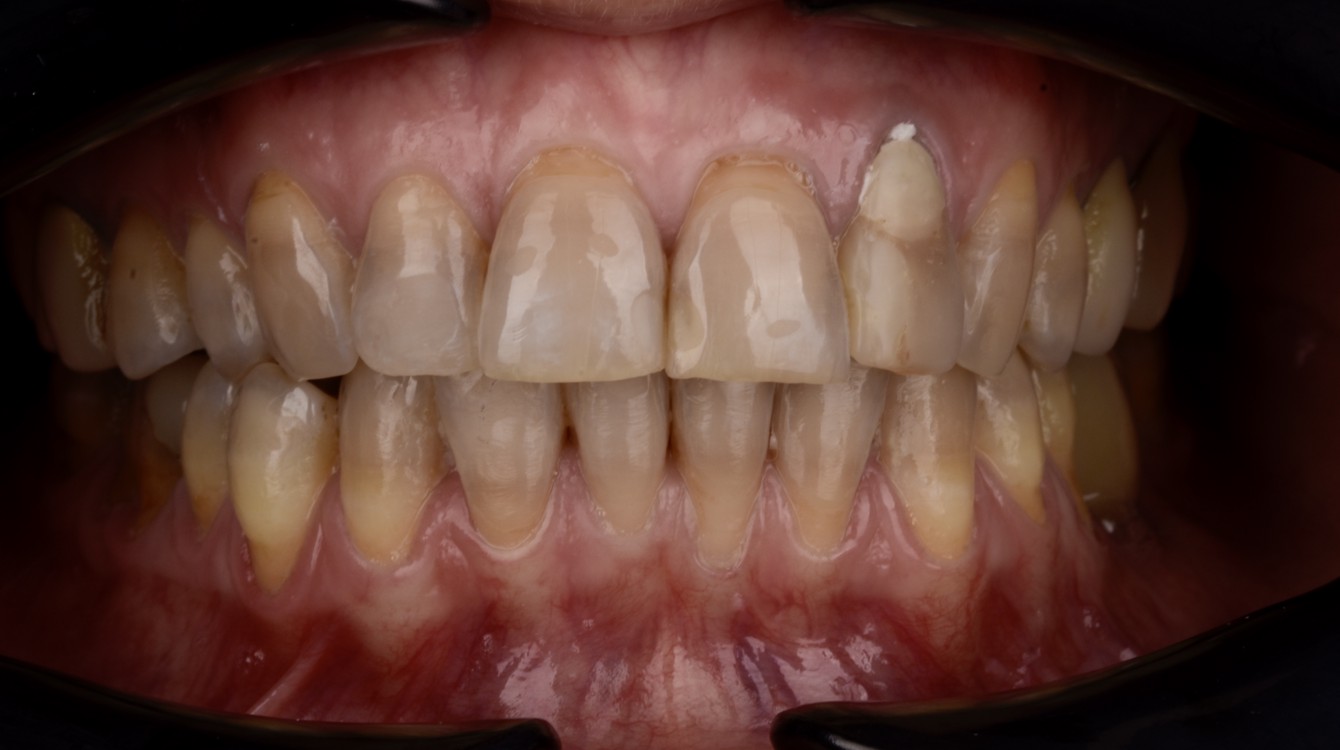

Nach einer umfassenden Untersuchung und Beratung empfahlen wir die Anfertigung von Einzelkronen aus Zirkonoxid sowie die chirurgische Abdeckung der Rezessionen im Unterkiefer. Um den Behandlungsplan für die Patientin möglichst anschaulich darzustellen, wurde ihr neues Lächeln mithilfe des Digital Smile Design (DSD) präzise entworfen.

Romina war aktiv an der Gestaltung ihres idealen Lächelns beteiligt und erhielt die Möglichkeit, das geplante Ergebnis vorab zu betrachten. Die Patientin zeigte sich äußerst zufrieden mit der Präsentation, woraufhin wir mit der Behandlung begannen. Die gesamte Therapie erstreckte sich über einen Zeitraum von drei Monaten.